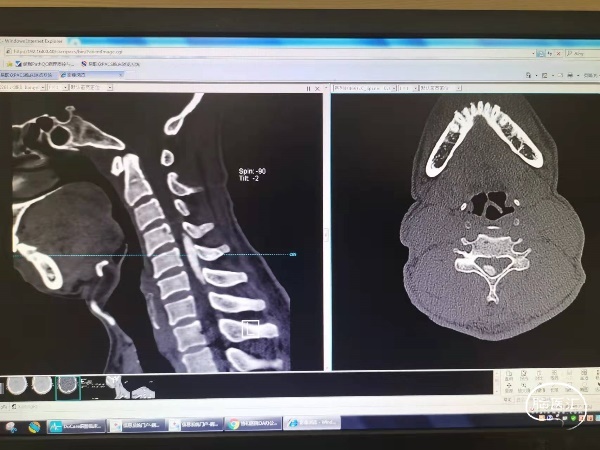

图1 术前颈椎CT三维重建示患者左侧C3-4黄韧带骨化,右侧C4-6黄韧带骨化。

图2 术前MR示患者左侧C3-4黄韧带骨化,右侧C4-6黄韧带骨化,并脊髓受压水肿。